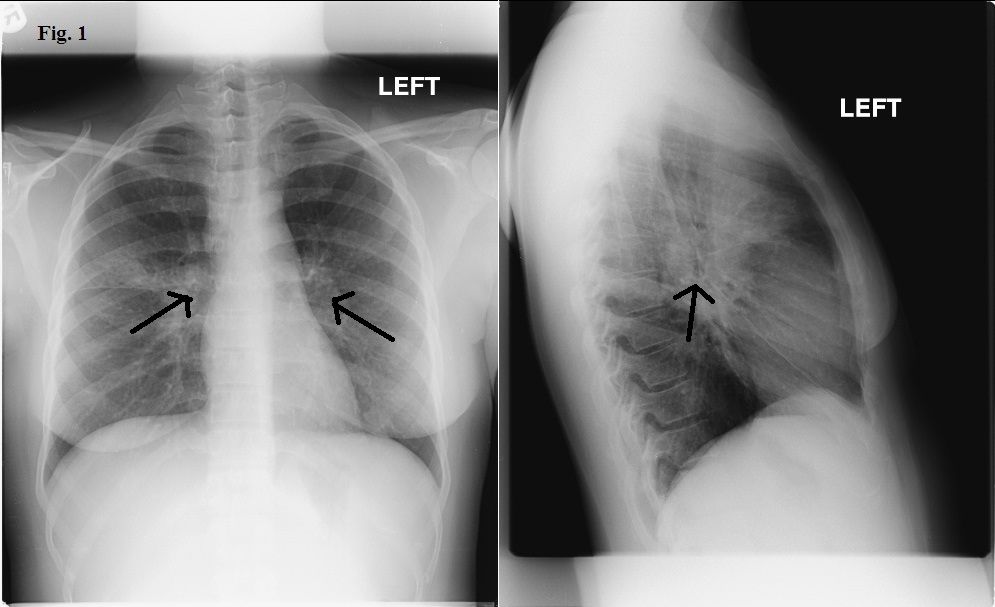

Figure 1. Chest x-ray film 1 year before presentation.

A chest radiograph obtained 1 year earlier was notable for mild hilar prominence (Figure 1). (Click on images to enlarge.) A repeated chest radiograph showed new bilateral diffuse interstitial infiltrates involving both lungs, along with bilateral hilar lymphadenopathy (Figure 2). A chest CT scan showed similar findings with a tree-in-bud appearance predominantly in the midlung zones and perihilar areas (Figure 3). Tree-in-bud appearance describes a CT finding of centrilobular opacities which correspond to luminal impaction of bronchioles that become focally dilated with fluid, pus or mucus. Also seen was bilateral axillary, hilar, precarinal, and subcarinal lymphadenopathy. Pulmonary function testing (PFT) results showed a progression from moderate to severe obstructive lung disease and worsening diffusing capacity of the lung for carbon monoxide (DLCO).